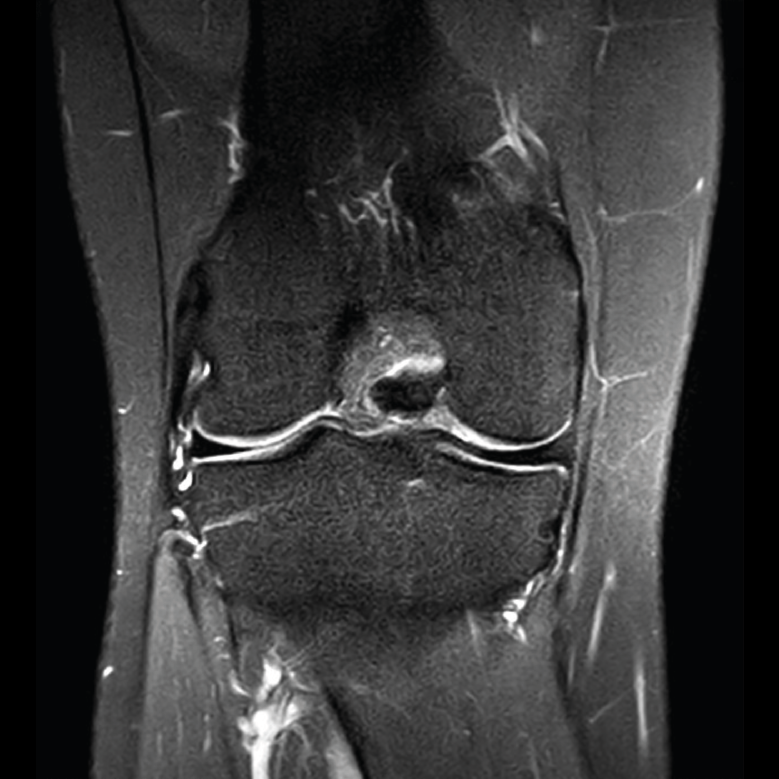

4.3. Osteocondritis

En la osteocondritis se aprecia una lesión subcondral caracterizada por resorción ósea, colapso y la formación de un secuestro.

El estudio por RM es una herramienta valiosa para diagnosticar e identificar las lesiones del cartílago. Conocer el aspecto del cartílago y saber cuánto y cuándo se lesiona, basándose en las clasificaciones actuales, permiten al radiólogo proporcionar la máxima información al clínico(20).

Figura 53. Corte de secuencia sagital (A) y axial (B) T2 Fat-Sat de RM de rodilla: lesiones osteocondrales en el fémur y la rótula.

Numerosos estudios demuestran la utilidad de la RM para definir la estabilidad o inestabilidad de la lesión en la osteocondritis, destacando su carácter no invasivo y la capacidad de valorar la progresión y la respuesta al tratamiento(21)(Figuras 53 y 54).

Figura 54. Corte de secuencia T1 y T2 Fat-Sat coronal de resonancia magnética: gran osteocondritis en el cóndilo femoral interno con edema en la medular adyacente.